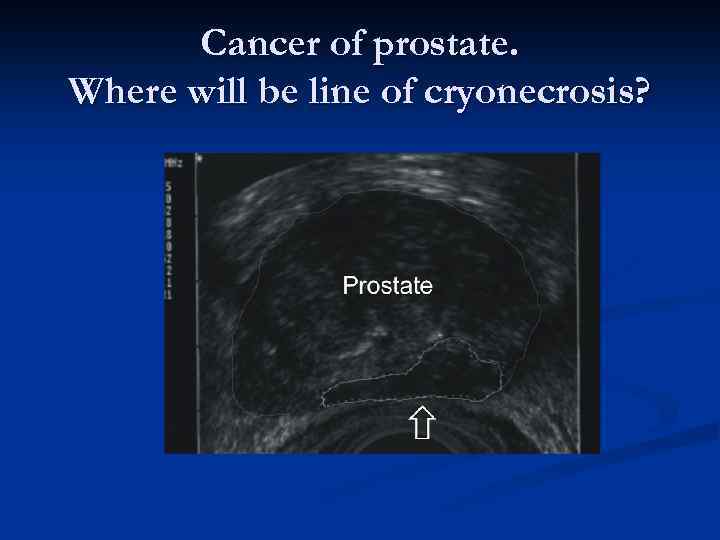

Cancer of prostate. Where will be line of cryonecrosis?

Cancer of prostate. Where will be line of cryonecrosis?